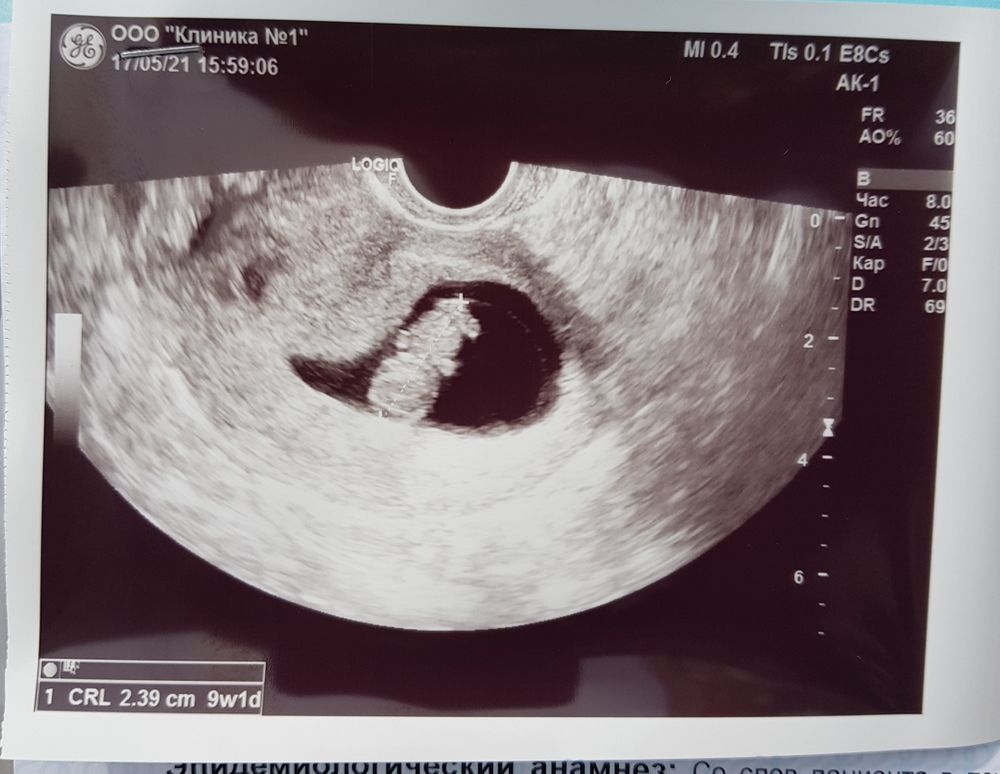

Сегодня не выдержала и снова пошла к своему врачу в ЖК,как и ожидалось она мне ничего внятного не сказала. Хотя пришла с болями с левой стороны живота. Прописала B6 и приходить по записи 1го июня. Еще сказала, если есть возможность, пойди сделай УЗИ. А я и пошла, потому что переживаю очень из-за того,что была и замершая, и внематочная. Плюс ко всему у меня нет,как мне кажется признаков беременности. Грудь не растёт, ни на что не тянет, не тошнит. И меня это напрягало. Ну слава Богу,сказали всё хорошо. Единственное по последним месячным у меня сегодня 9+6, а по УЗИ 9+1. Но думаю это не критично. Я увидела как мое сладкое солнышко двигает ручками🥰 услышала сердечко ❤Непередаваемые ощущения😊

Болеть сказали может из-за кисты,она немаленькая. А так всё отлично. Ттт. 🙏Через 2 недели скрининг. Жду с нетерпением.